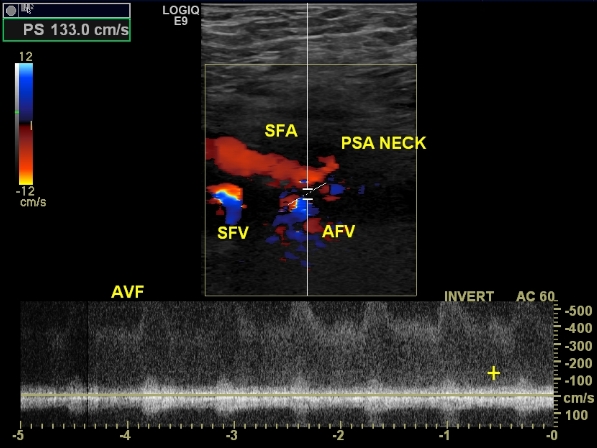

An arterio-venous fistula is diagnosed by using a duplex ultrasound. The following measures are looked for when diagnosing an arterio-venous fistula:

- When visualizing the common femoral artery and vein using color doppler, turbulent blood flow is noticed.

- The blood flow in the artery at the site of the fustula may show reduced velocities, as it heads toward the low resistance vein.

- The blood flow in the vein at the site of the fistula may show arterial characteristics. Following the vein proximally toward the heart shows gradual dampening of the effect.

In both cases of pseudoaneurysm and arterio-venous fistula, visualization should be made carefully from the level of the external iliac vessels and down toward the femoral vessels, as not to miss a finding.